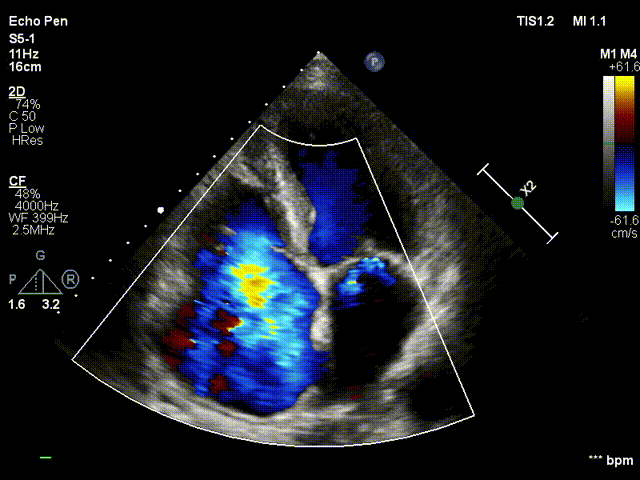

术后TTE:食道中段view提示三尖瓣轻度反流

3DTEE显示双房及右室扩大(RA52mm×50mm;RV31mm);左房及左心耳未见附壁血栓;左室下壁基底段运动减弱;三尖瓣环左右径38mm,三尖瓣前叶长度24.5mm,后叶 长度25.7mm,三尖瓣隔叶长度15.7mm,三尖瓣后隔gap3.1mm;前隔gap2.3mm,三尖瓣 TAPSE16mm;余各瓣膜回声纤细柔软,开放幅度正常;未见心包积液。2、彩色及频谱多普勒显示:收缩期三尖瓣口反流束主要来源于前隔交界,前隔交界反流束缩流颈宽度6.7mm,后隔交界反流束缩流颈宽度5.8mm;舒张期三尖瓣口平均跨瓣 压差1mmHg;收缩期二尖瓣口可见微量反流信号;舒张期主动脉瓣口反流束缩流颈宽 度3.0mm;PAPs35mmHg。